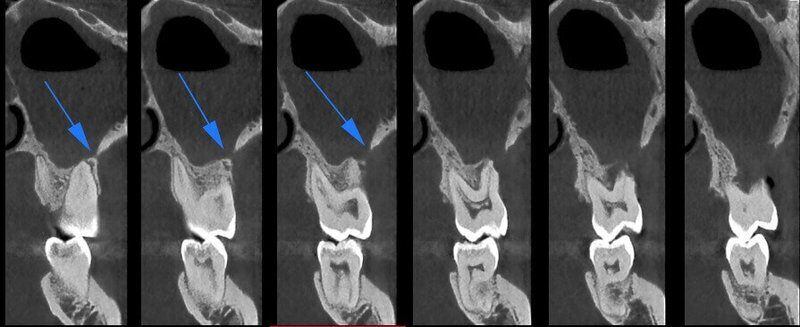

ATM Bocca Aperta